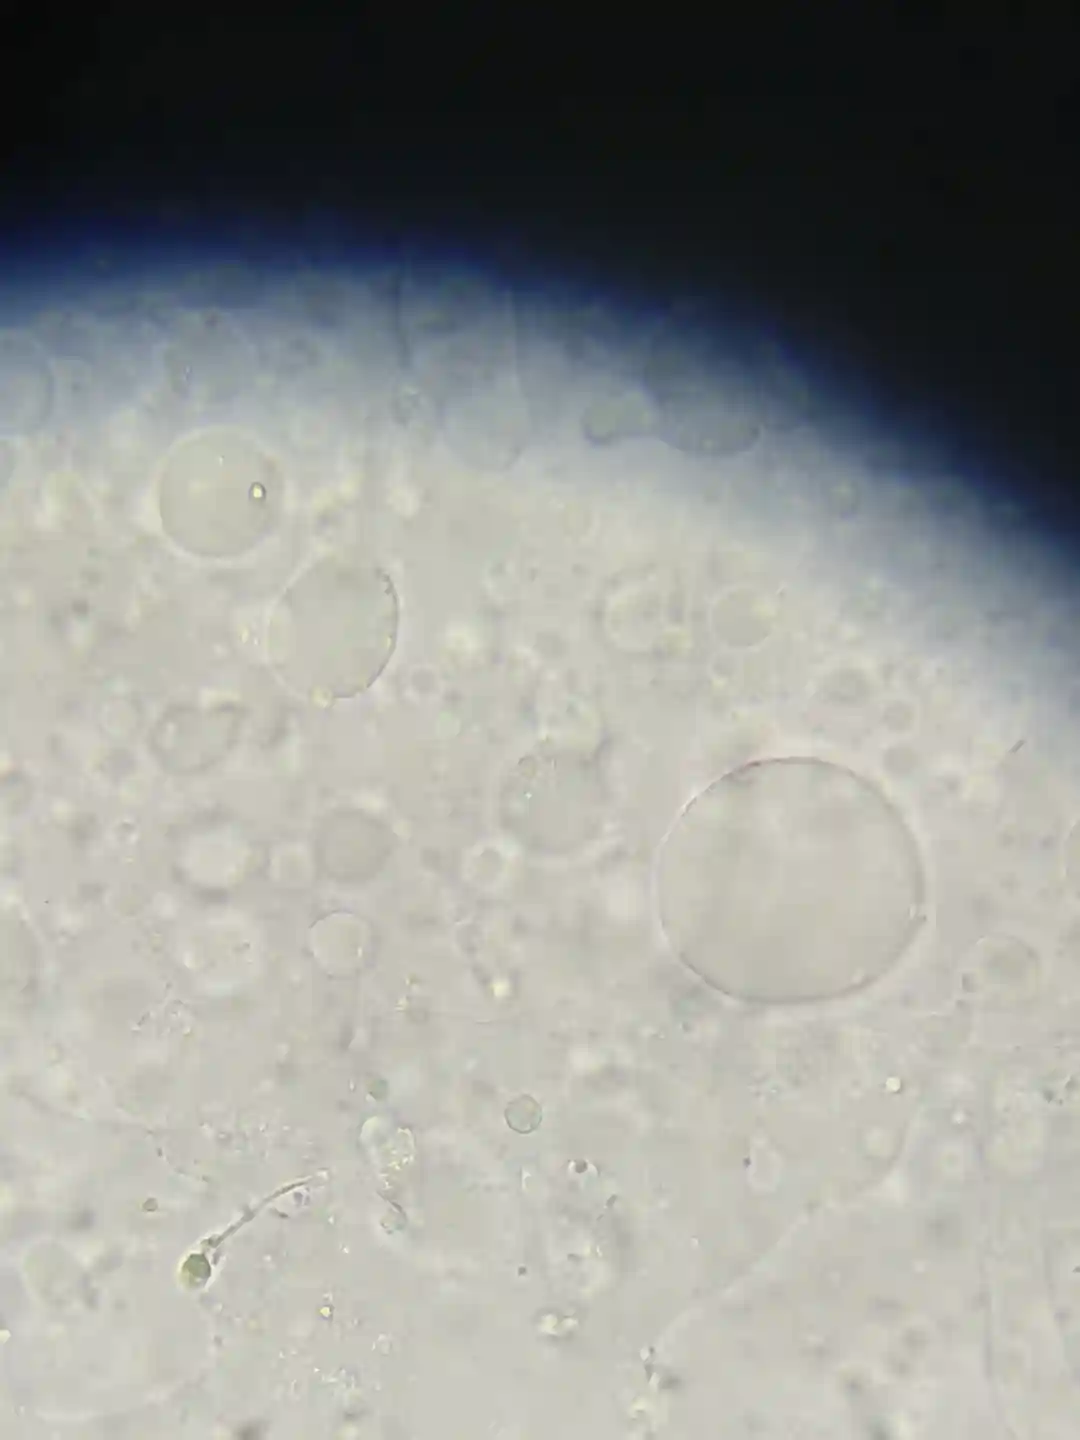

有没有这种情况在做试管的,我老婆一年前去佛山妇幼取卵结果当天无精,然后冻卵跑去中六了。现在基本弃用了,因为感觉那边医生不负责任技术也差。这个月准备取卵了,不知道这种情况做二代有没有希望,张靖医生说他们医院少弱精的成功率都是56%。

染色体没问题,Y微缺失没问题,FSH5-7浮动,🥚🥚大概6.7ml偏小。目前在吃Q10,VE,锌硒片,蕃茄红素,氯米芬片。

小红书里我看到过和我一样的朋友也是单精子冷冻找了几条较好的活动精子做试管然后生了孩子的